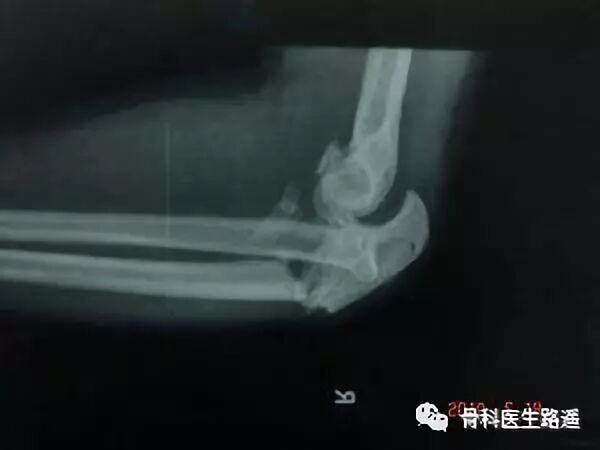

骨科医生判断一个骨折是否严重,并不是看骨折碎没碎,而是看骨折有没有破坏累及到关节面。

这是因为关节就像轴承一样,要不停的运转,需要关节面极其的平整和光滑。如果关节面因为骨折不平整光滑了,哪怕只是几毫米的移位台阶,也是不允许的。

以前没有X光片,更没有CT,对关节面平整的追去也没有那么完美,所以也造成了骨折后的各种创伤性关节炎。比如,很多人脚后跟骨折后,保守治疗虽然骨折能长好,但是一踩地就疼,最后瘸了就是这个原因。

后来有了X光片,尤其是CT后,医生们发现很多复杂的关节内骨折,如果不做手术切开,不在肉眼直视下看着关节面复位,隔着皮肉只依靠感觉手法复位,是无法达到毫米级的高要求的。所以,对于这部分骨折,保守治疗的确能让骨折长好,但是也只能做到这里。而选择手术,则是为了患者能获得更多的收益,比如:无痛的负重和优良的功能。